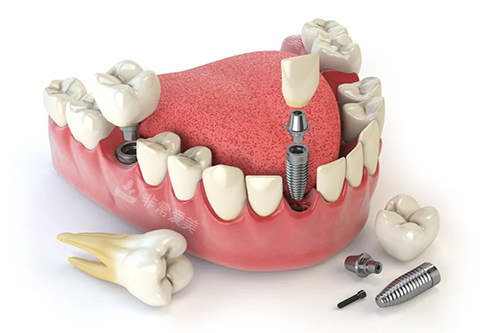

而在种植牙领域,乐美口腔更是有着出色的表现。

可靠的医生团队会根据患者的口腔状况、骨质条件等制定个性化的种植方案,采用较高的种植技术和优质的种植体,让患者能够拥有如同真牙一般的咀嚼体验。

牙齿种植卡通示意图